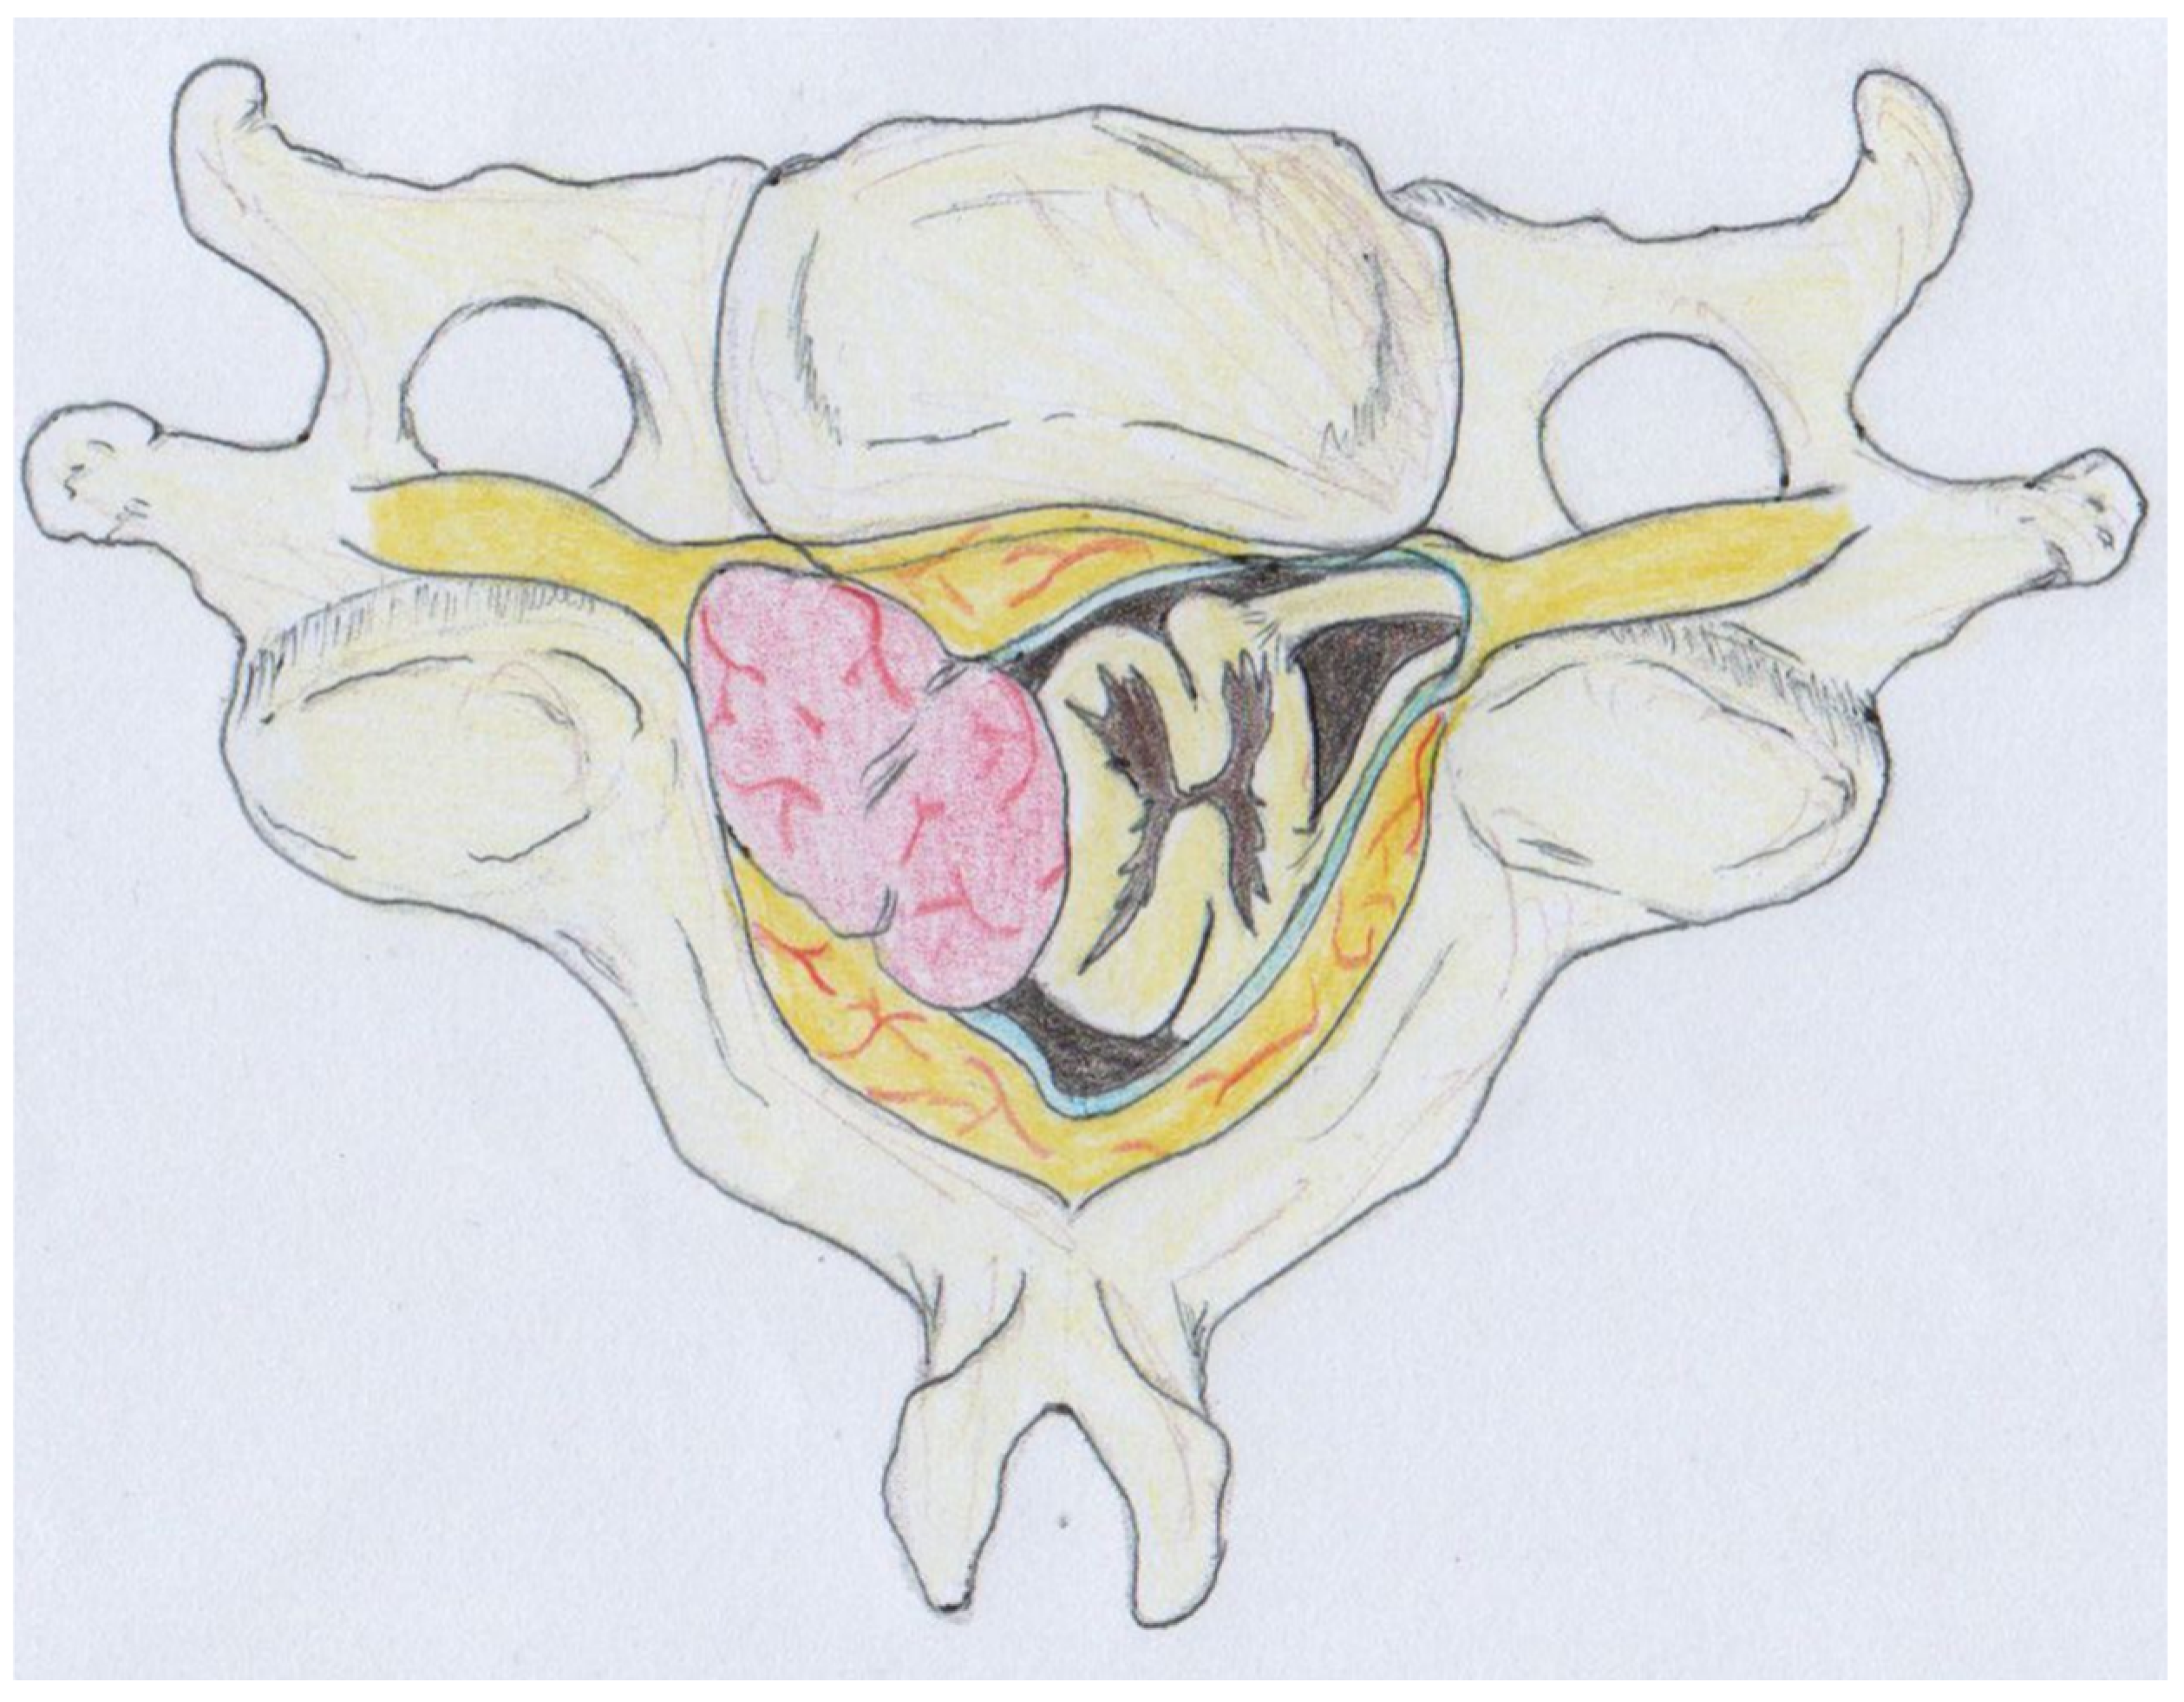

This approach facilitated a safe surgical route despite the tumor’s size, which was causing gradual spinal cord displacement (Figure 5).

Figure 5.

Illustration demonstrating the presence of the intradural extramedullary tumor causing gradual displacement of the spinal cord. Despite the tumor’s size, the surgical approach facilitated a safe route for intervention. Histological examination documented a schwannoma showing degenerative changes and diffuse hypocellular ischemic areas (ancient schwannoma).